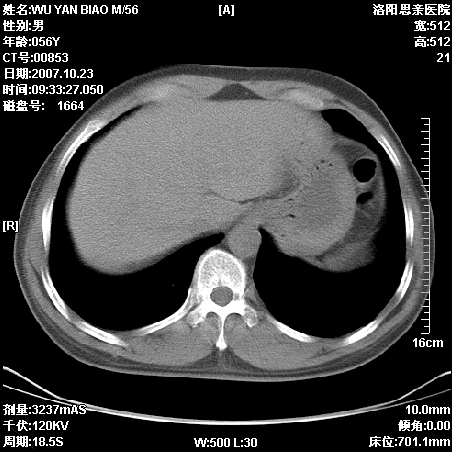

标题: CT10160:M56Y,体检发现,病人无不适,病人随访中 [打印本页]

标题: CT10160:M56Y,体检发现,病人无不适,病人随访中

后上纵隔占位,与肺交界清,宽基底附着脊柱,密度均匀,局部骨质无明确改变.

考虑;神经源性肿瘤,---起源交感n链?,不除外肠源性囊肿.

1、病灶在后纵隔脊柱旁沟内,此处是神经原性肿瘤的好发部位

2、病灶边缘光滑整齐,更说明病灶来于纵隔,由于有胸膜的包裹所以才导致这么光滑的边缘

3、病灶内的密度均匀